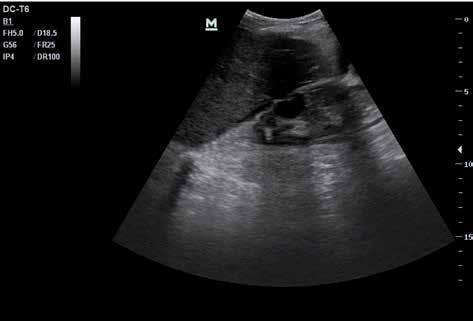

4.1 Freie abdominelle Flüssigkeit

Von freier abdomineller Flüssigkeit (FAF) spricht man, wenn sich im Ultraschall echofreies Material im Bauchraum (intraperitoneal) findet. Normalerweise ist in der Bauchhöhle keine Flüssigkeit zu erwarten, d. h. der sonografische Nachweis von freier intraabdominel ler Flüssigkeit ist immer als pathologisch anzusehen. Freie Flüssigkeit muss aber nicht in jedem Fall Blut sein. Freie Flüssigkeit aufgrund einer anderen Vorerkrankung wird auch als „Aszites“ bezeichnet. Aszites ist Flüssigkeit, die entweder aktiv in die Bauchhöhle sezer niert wird oder passiv aus den Gefäßwänden austritt.

Die Unterscheidung zwischen einer Blutung in die Bauchhöhle und einer anderen Ursa che der FAF ist präklinisch oft nur anhand der Wahrscheinlichkeit möglich. Für eine end gültige Diagnosesicherung ist eine Punktion notwendig. Oft hilft aber der gesunde Men schenverstand – bei einem akut außerorts mit dem Motorrad verunglückten jungen Mann mit freier abdomineller Flüssigkeit ist ein Aszites durch Leberzirrhose nicht unbedingt die wahrscheinlichste Diagnose.

Zunächst sammelt sich mögliche freie Flüssigkeit an drei typischen präformierten Stel len im Bauchraum und kann hier sonografisch dargestellt werden. Dies sind der MorisonPouch, der Koller-Pouch und der Douglas-Raum (von engl. „Pouch“ für „Beutel“, Abb. 34 –36).

Der Morison-Pouch ist eine Aussackung des Peritoneums zwischen Leberunterrand und rechter Niere. Dem entspricht auf der Gegenseite der Koller-Pouch zwischen Milz und linker Niere. Der Douglas-Raum befindet sich dorsal hinter der Harnblase und zieht bis ins kleine Becken.

Je nach Menge der freien Flüssigkeit ist in den beschriebenen Räumen ggf. nur eine schmale echofreie Lamelle zu erkennen, bei erheblichen Mengen freier Flüssigkeit ist diese aber auch im ganzen Bauchraum sichtbar. So sieht man bei Patienten mit fortge schrittener Leberzirrhose oftmals im ganzen Bauch nur noch „schwarz“, und darin einge bettet die parenchymatösen Oberbauchorgane ebenso wie den Darm.

Abb. 37 ˘ Freie Flüssigkeit (FAF) (1) im Morison-Pouch. Rechtsseitiger Flankenschnitt Abb. 38 ˘ Freie Flüssigkeit (FAF) (1) im Koller-Pouch. Linksseitiger Flankenschnitt